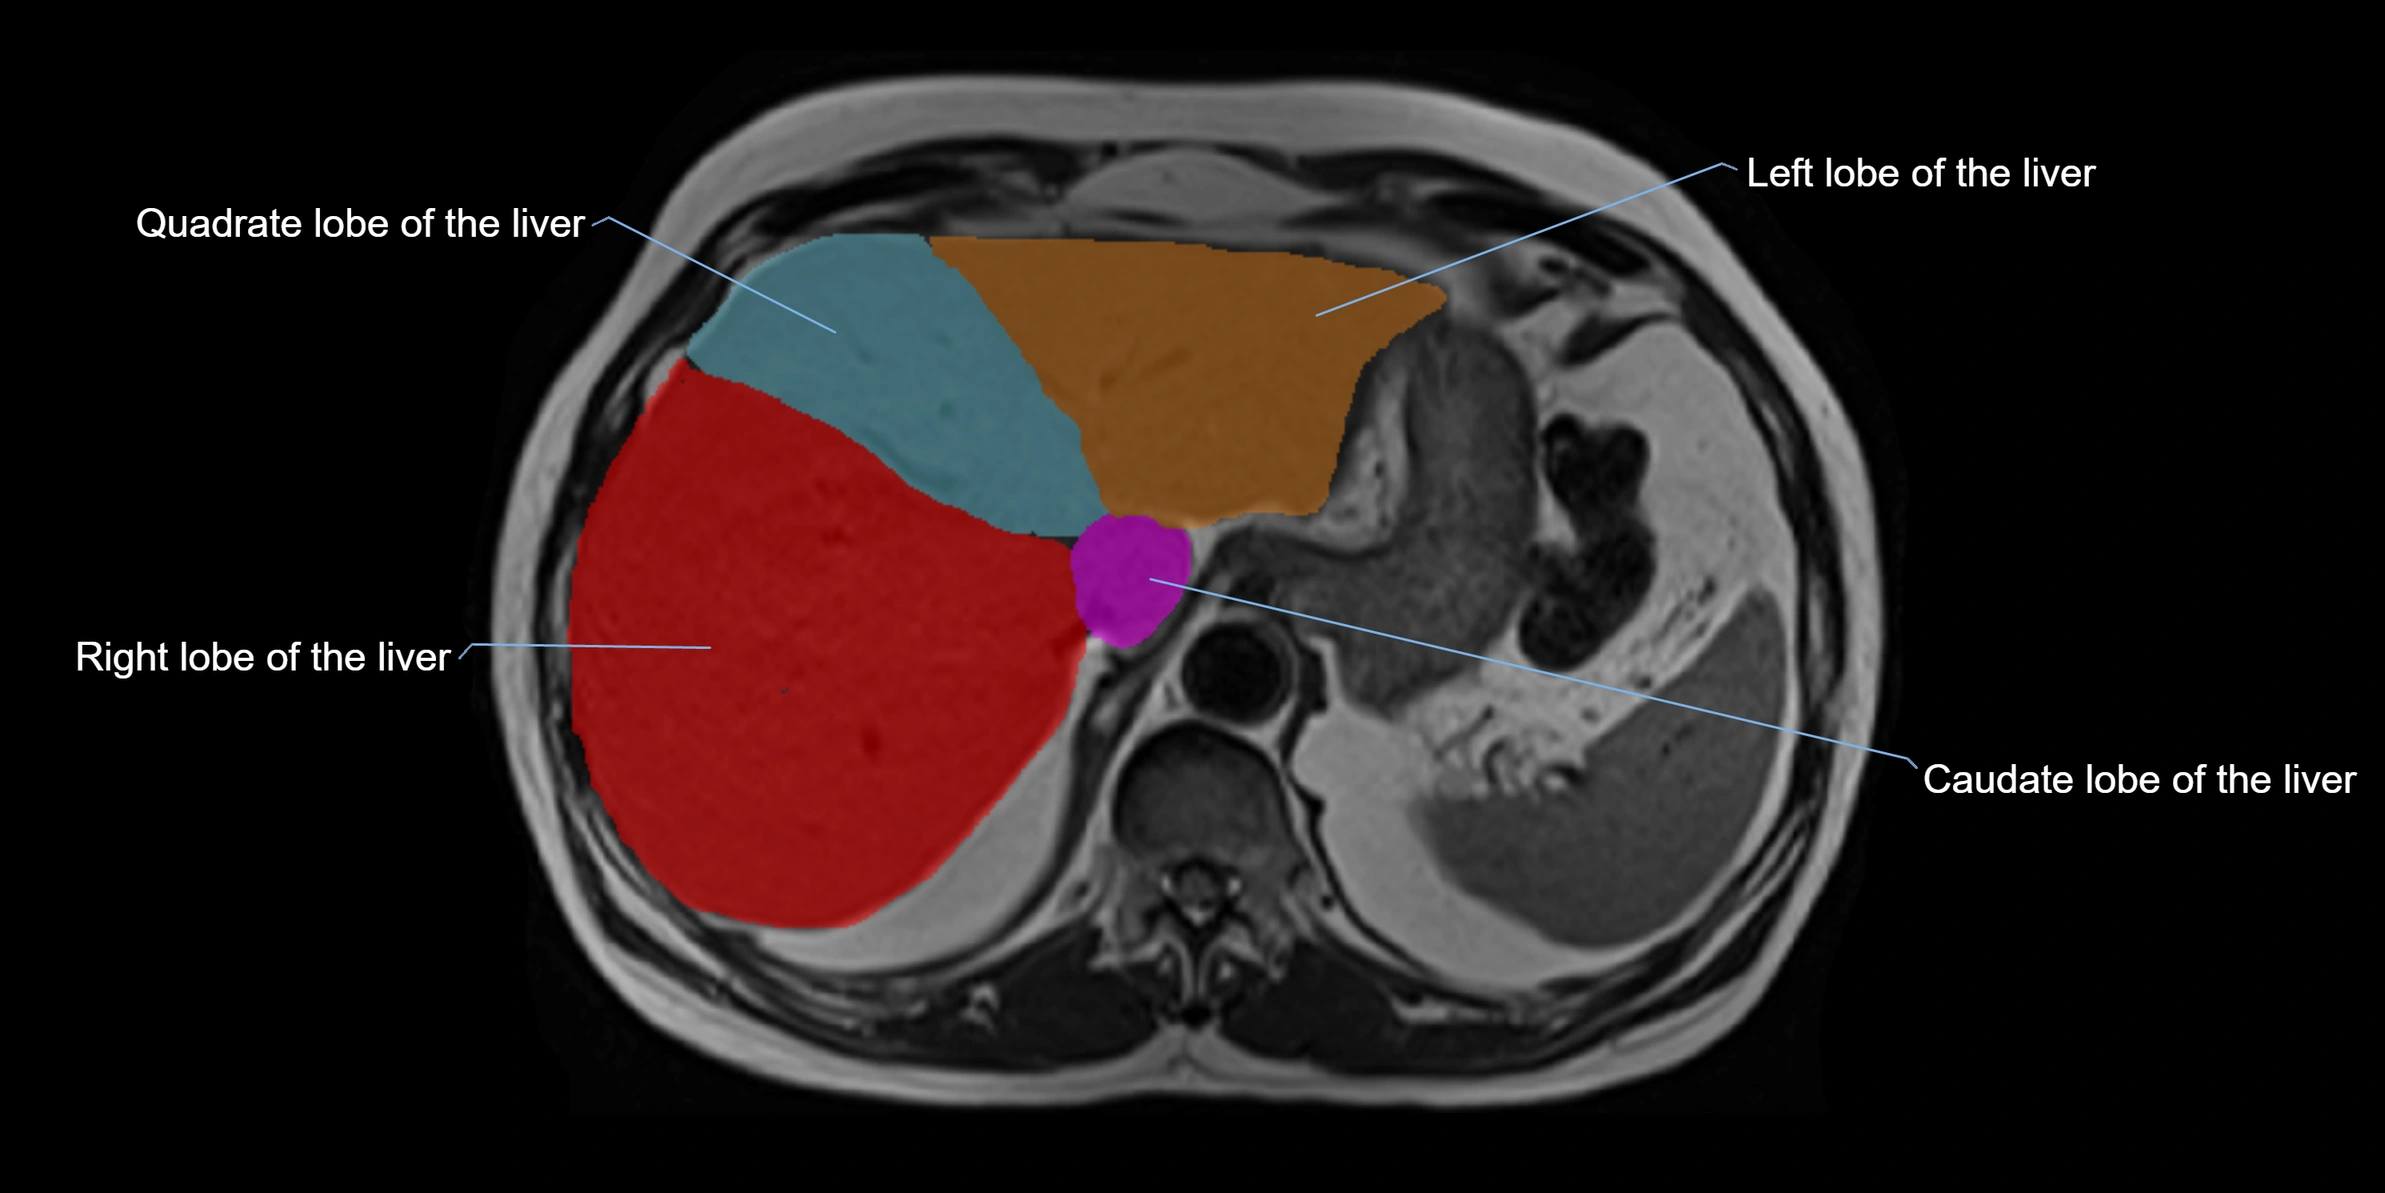

The caudate lobe of the liver is a distinct anatomical subdivision of the liver, designated as segment I in Couinaud’s classification. It lies on the posterior surface of the liver, between the fissure for the ligamentum venosum (left boundary) and the groove for the inferior vena cava (IVC) (right boundary). Superiorly, it is related to the posterior liver surface, and inferiorly it is separated from the left lobe by the porta hepatis.

MRI image

image